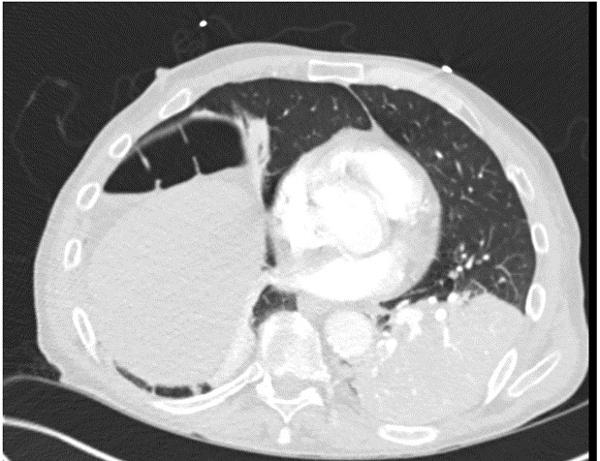

A chest x-ray done prior to intubation showed concern for free air below the right diaphragm (Image 1). A subsequent CT scan showed dense left lower lobe consolidation and confirmed a gaseous collection between the right hemidiaphragm and the liver (Image 2).